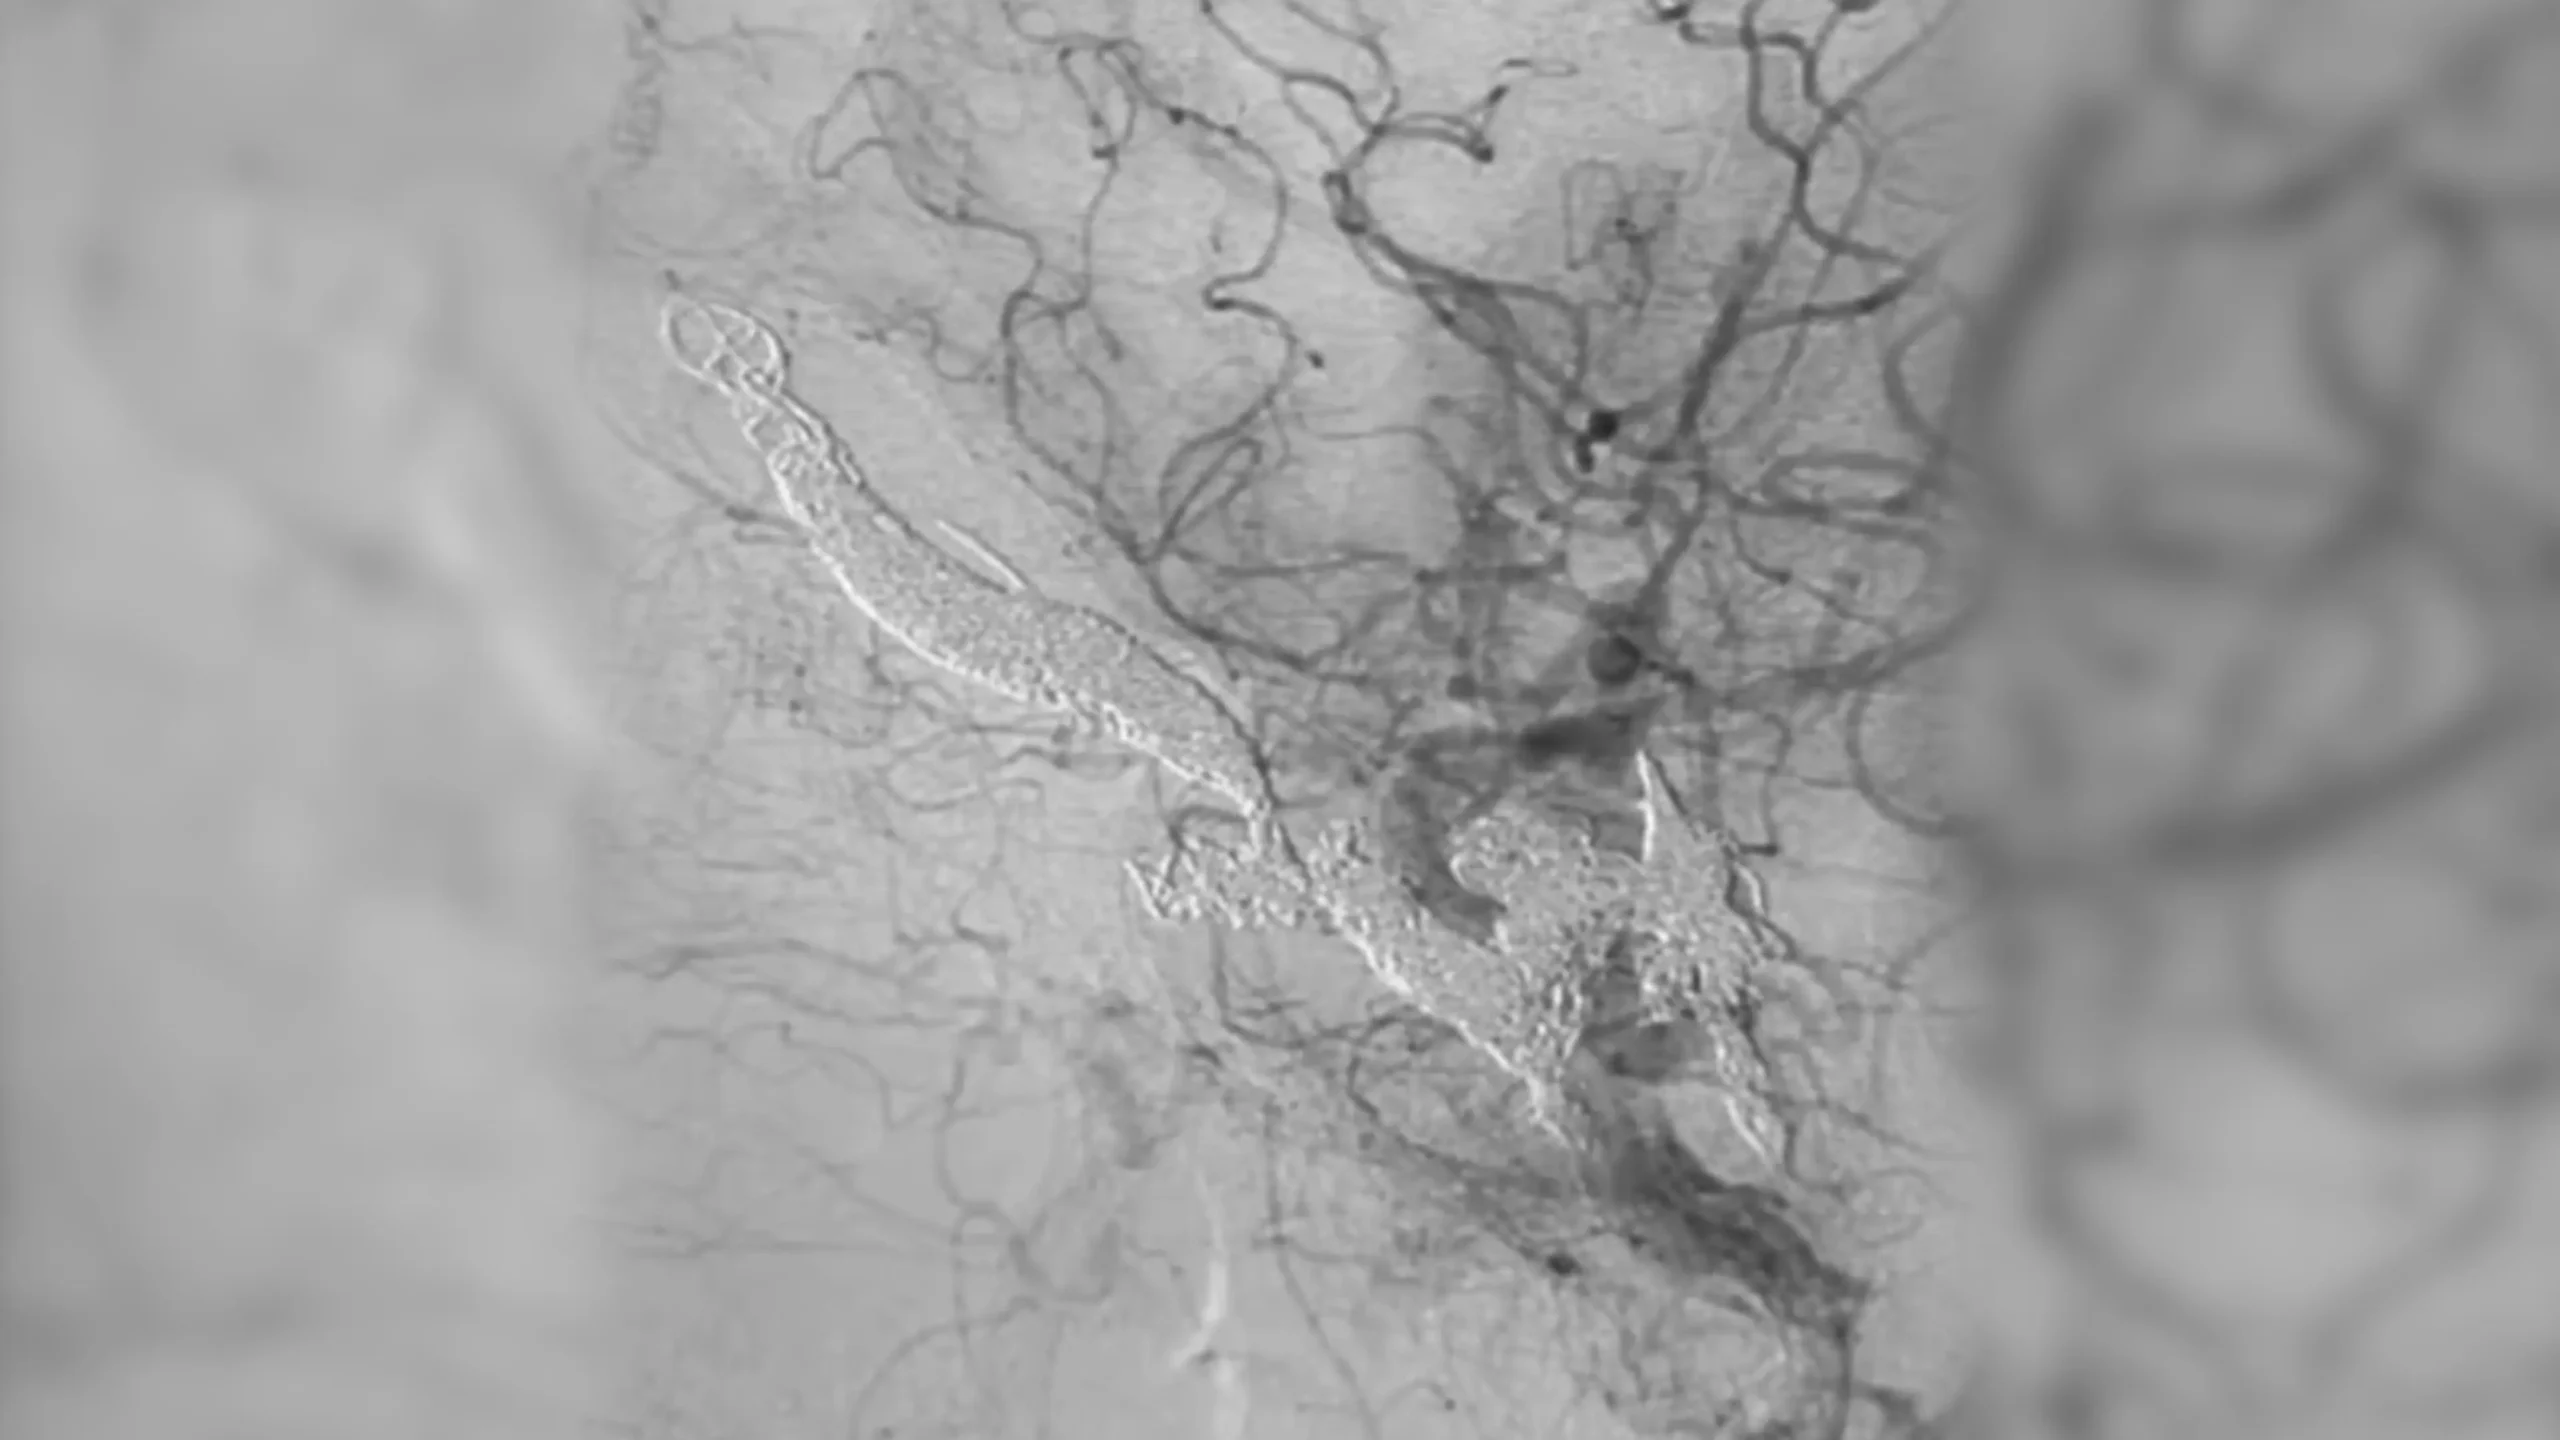

angiogram of a fistula

Direct CC fistula managed with two complex coils and SwiftPAC: 60 cm, 30 cm, 15 cm

CC Fistula

• PC400 and SwiftPAC designed for complex fistulas

• Offered high volume, flexible design, and embolization

• BENCHMARK family is designed to facilitate the therapy of a wide range of conditions